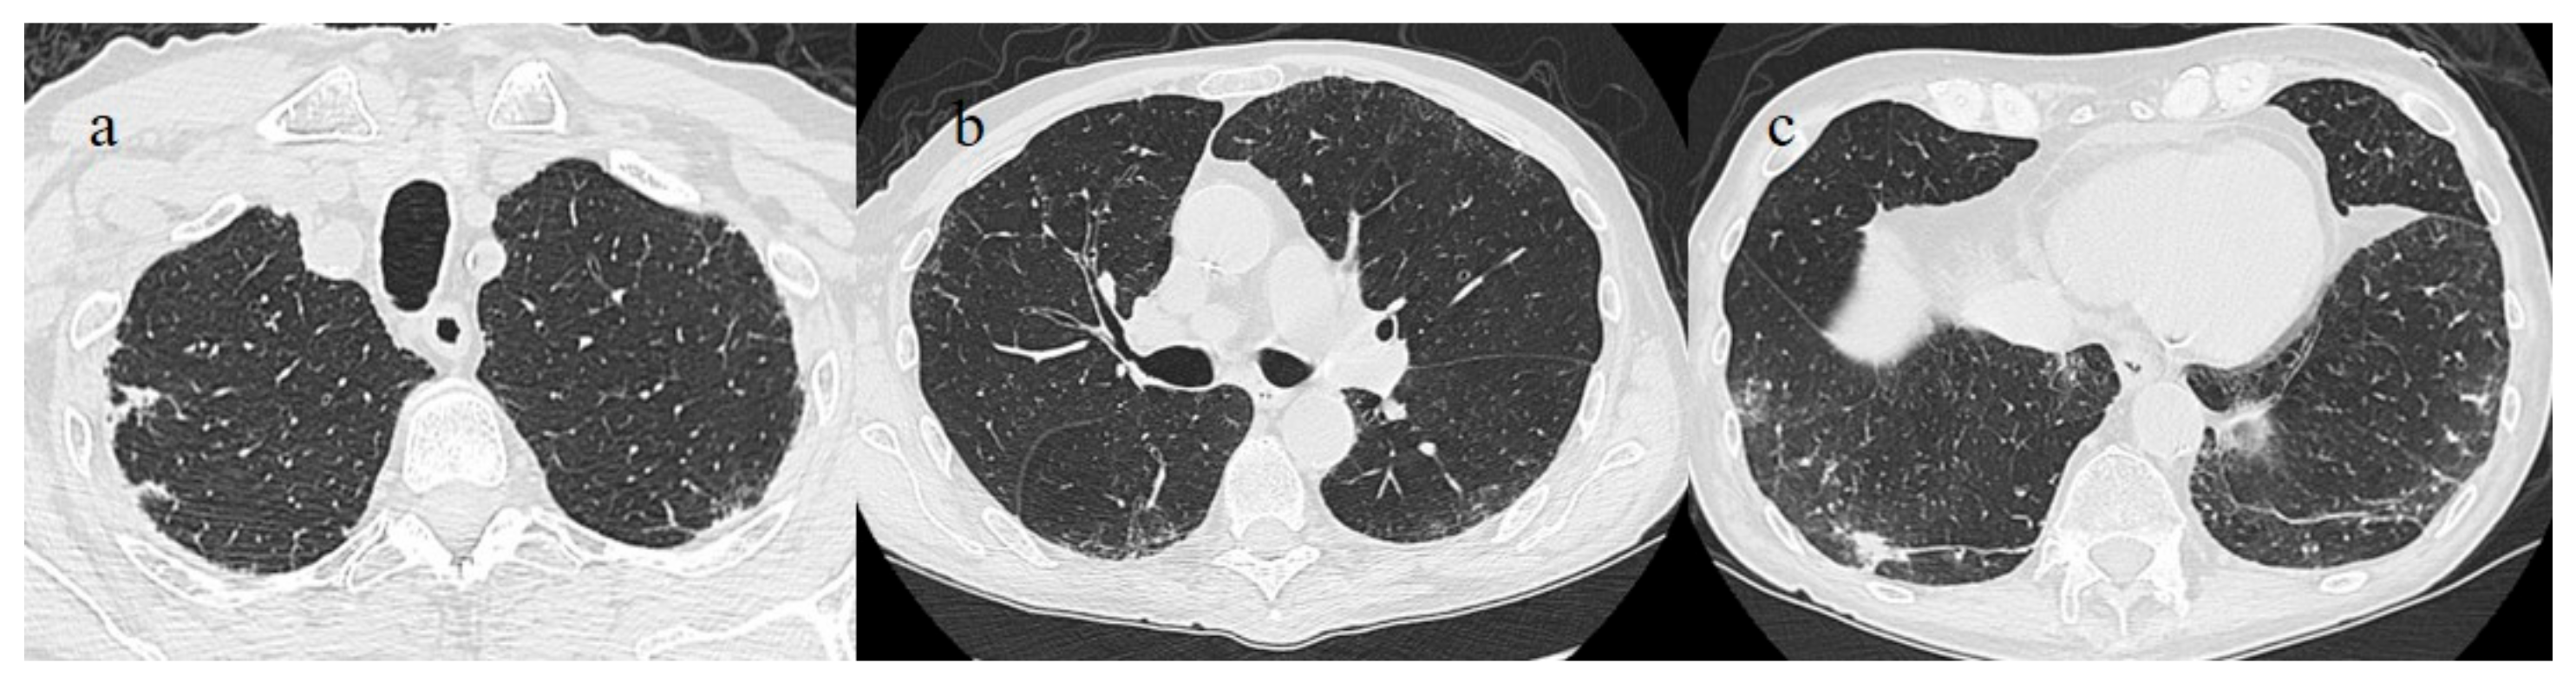

6. Case #5

A 63-year-old woman visited the emergency department of our hospital on 30 July with fever and dyspnea with also thoracic pain. She had a history of previous uterine cancer treated with surgery 10 years before. She had already tested positive for SARS-CoV-2 on 21 July 2021 on an OP/NP swab conducted by an authorized laboratory. She was also fully vaccinated with the COVID-19 mRNA-1273 Pfizer vaccine (first dose on 22 April and second dose on 14 May). She was treated with an oral administration of azithromycin (500 mg 1 cp once daily) for 3 days by her family doctor. However, 2 days before hospital admission, she reported nausea and vomiting. At the time of hospital admission, an NP/OP swab tested positive for SARS-CoV-2, however, without the detection of any variants. The woman reported that her relatives, including her husband and daughter, were also fully vaccinated against COVID-19, and they had also tested positive for SARS-CoV-2. Her daughter reported recent contact with her boyfriend, who had also tested positive for SARS-CoV-2 prior to the daughter’s COVID-19 infection. The daughter’s boyfriend was also fully vaccinated. On hospital admission, during laboratory examination, the woman showed mild elevations in CRP (3.98 mg/dL), LDH (309 IU/L), and the D-dimer (0.51 mg/L). The other laboratory values were within the normal range. Her SO2 level was at 94%. However, due to also to the history of previous uterine cancer and the presence of dyspnea a chest CT was made in an emergency. On the chest CT, some GGO areas were found in a peripheral distribution, suggesting COVID-19 pneumonia with a CT-SS of 5/20 (Figure 9). No serology for SARS-CoV-2 was performed. Treatment with ceftriaxone (1 g once daily with intravenous administration) was started, together with dexamethasone (4 mg once daily with intravenous administration) and LMWE 4000 IU (once daily with a subcutaneous administration). The patient’s clinical conditions improved, and she was discharged after 3 days.

Figure 9. Chest CT performed on 21 July showing some central and peripheral GGO with interstitial thickness and multifocal distribution in the superior lobes (a), in the middle and inferior lobes (b) and in the inferior lobes (c).